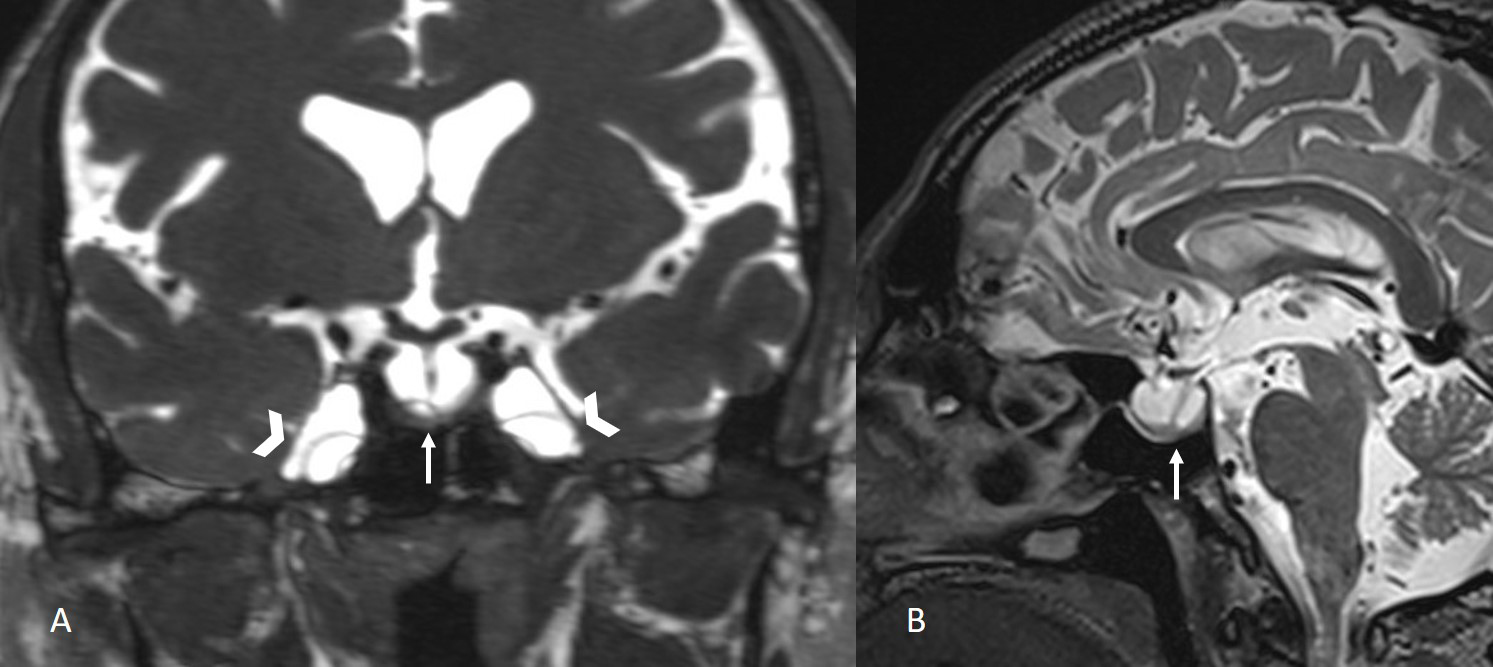

The institutional review board approved this single-center retrospective study. Patients with suspected CSF leakage who underwent MRI with a special protocol between 2012 and 2023 were evaluated. Images of 240 consecutive patients were assessed for CSF leakage by two neuroradiologist with 10 and 3 years of experience. Patients with leakage from sites other than the sphenoid sinus were excluded from the study (n = 220). Six out of 20 patients with a history of trauma or surgery of the sphenoid sinüs or cavernous sinus were also excluded. The remaining 14 patients with sphenoid sinüs CSF leakage formed the study group. Leakage was supported by surgical findings and beta-2 transferrin test. All imaging was performed using 3 Tesla (Verio, Siemens, Erlangen, Germany) or 1.5 Tesla (Aera, Siemens, Erlangen, Germany) MR scanners. The MRI protocol for CSF leakage consisted of T2 weighted fat suppressed coronal plane images with 3 mm slice thickness, T2-weighted sagittal plane SPACE images with 1 mm slice thickness, and CISS coronal plane images with 1 mm slice thickness. All images were evaluated by two radiologist with 4 years of experience in terms of empty sella, enlargement of the Meckel's caves (Figure 1), fluid in the optic nerve sheaths, vertical tortuosity of the optic nerves (Figure 2), arachnoid pits, encephaloceles (Figure 3), and lateral recess pneumatization of the sphenoid sinuses. Lateral recess pneumatization was defined as pneumatization lateral to the line connecting the foramen rotundum and the Vidian canal (Figure 4). The side of the leakage and the other accompanying sites of leakage were noted. The presence of a bony defect was evaluated on CT images (Figure 5).Descriptive statistics were used for data analysis. Continuous variables were presented as mean ± standard deviation [median (minimum?maximum)], and categorical variables were expressed as frequency and percentage.

![]() Büyütmek İçin Tıklayın |

Figure 1: Coronal CISS image and sagittal T2-weighted SPACE image show empty sella (arrows) and enlargement of the Meckel's caves (arrowheads). |